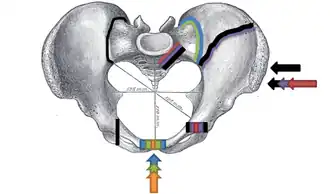

Young-Burgess classification

The Young-Burgess classification system is based on mechanism of injury: anteroposterior compression type I, II and III, lateral compression types I, II and III, and vertical shear,[6] or a combination of forces.

Lateral compression (LC) fractures involve transverse fractures of the pubic rami, either ipsilateral or contralateral to a posterior injury.

- Grade I – Associated sacral compression on side of impact

- Grade II – Associated posterior iliac ("crescent") fracture on side of impact

- Grade III – Associated contralateral sacroiliac joint injury

The most common force type, lateral compression (LC) forces, from side-impact automobile accidents and pedestrian injuries, can result in an internal rotation.[10] The superior and inferior pubic rami may fracture anteriorly, for example. Injuries from shear forces, like falls from above, can result in disruption of ligaments or bones. When multiple forces occur, it is called combined mechanical injury (CMI). The best imaging modality to use for this classification is probably a pelvic CT scan.[11]

Open book fracture

One specific kind of pelvic fracture is known as an 'open book' fracture. This is often the result of a heavy impact to the groin (pubis), a common motorcycling accident injury. In this kind of injury, the left and right halves of the pelvis are separated at front and rear, the front opening more than the rear, i.e. like an open book that falls to the ground and splits in the middle. Depending on the severity, this may require surgical reconstruction before rehabilitation.[12] Forces from an anterior or posterior direction, like head-on car accidents, usually cause external rotation of the hemipelvis, an “open-book” injury. Open fractures have an increased risk of infection and hemorrhaging from vessel injury, leading to higher mortality.[13]